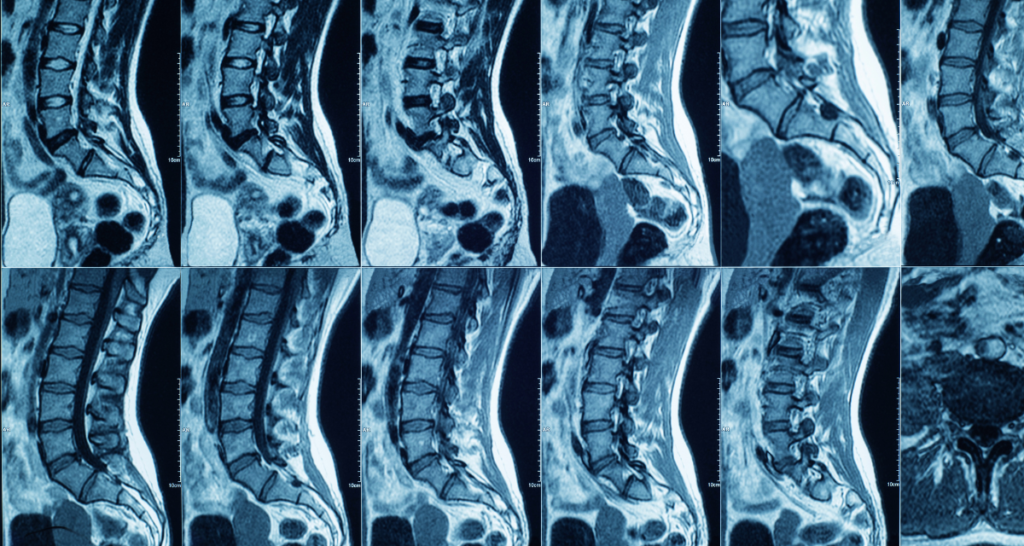

Spine MRI

You may see terms like disc bulge, nerve root, foraminal narrowing, or spinal canal. Many people have mild disc changes even without symptoms.